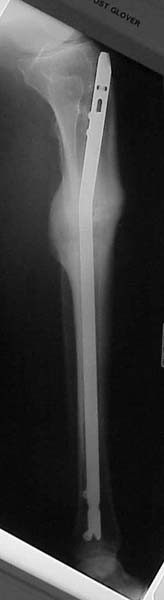

Thanks for the input on the tibia malunion w/ multiple plane deformity. I decided on a single cut osteotomy and IMN fixation based on desire to walk early, return to professor duties, and my previous experience w/ similar deformities (see another tibial malunion -below). The opening wedge was packed w/ a combination of autograft, allograft and demineralized bone.

Pt was 10 yrs s/p open tibia fx treated in a cast w/ IR, varus, 2 cm short, and recurvatum. He has done well post op.

intraop

18 mos postop